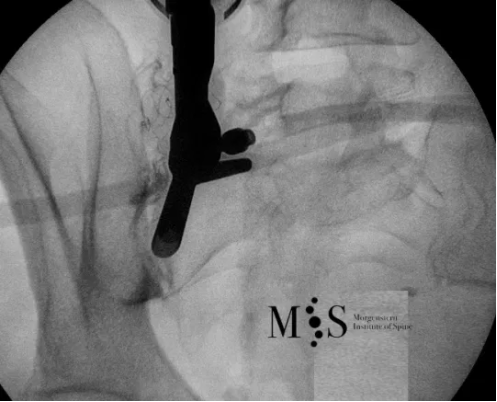

Imatge de fluoroscòpia intra-operatoria d’una endoscòpia de la articulació sacroiliaca.

Es pot veure com l’endoscopi está situat en el costat esquerre de la imatge asobre la articulació sacroiliaca

Els efectes analgèsics de la endoscòpia solen treure la dolor de forma significativa amb una duració en el temps que pot arribar a ser d’anys de duració. El Dr. Morgenstern es pioner en la utilització de la endoscòpia de la articulació sacroiliaca a Catalunya, Espanya i Europa. Aquesta intervenció endoscòpica es realitza amb anestèsia local, fent-se amb una incisió a la pell de menys de 1 cm de longitud lo qual permet una ràpida recuperació, amb alta hospitalaria en menys de 24 hores.